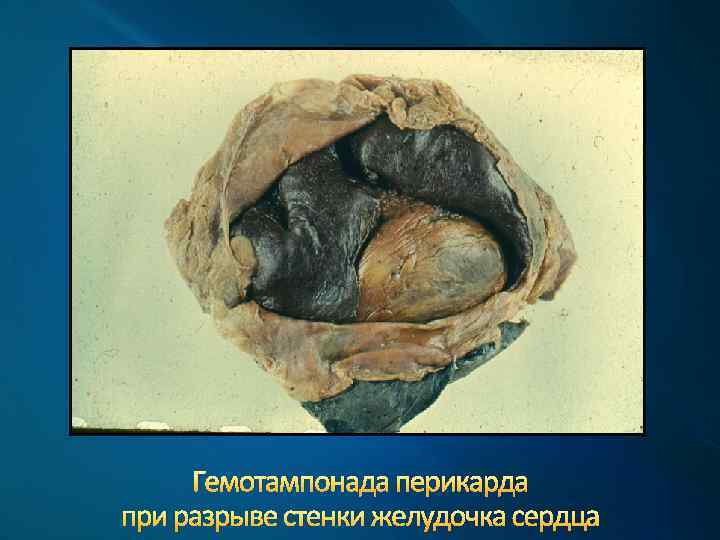

Гемотампонада перикарда при разрыве стенки желудочка сердца